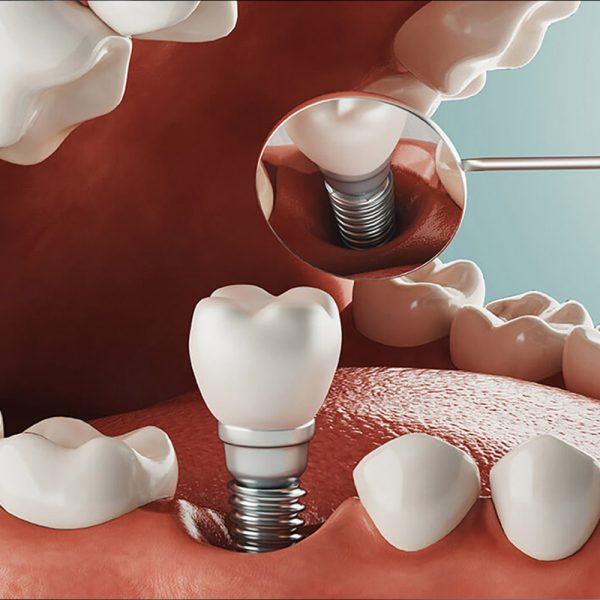

Implante Dentário

Implantes dentários: a solução definitiva para sorrisos completos. Substitua dentes ausentes com segurança e conforto, restaurando a função mastigatória e a estética. Beneficie-se de uma alternativa duradoura às próteses convencionais, revitalizando sua autoconfiança e qualidade de vida. Descubra como os implantes dentários podem redefinir seu sorriso.